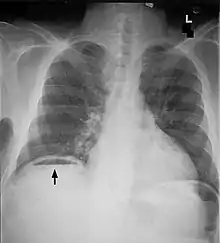

Bowel obstructions are commonly secondary to adhesions, hernias, or cancer. Bowel obstruction can be an emergency requiring immediate surgery. Original testing and imaging include blood tests for electrolyte levels, and abdominal X-rays or CT scans. Treatment often begins with IV fluids to correct electrolyte imbalances. Obstructions may be complicated by ischemia or perforation of the bowel. These cases are surgical emergencies and often require bowel resection to remove the cause of obstruction.[13] Adhesions are a common causes of obstruction, and frequently resolve without surgery.[14]

Bowel perforation presents with abdominal pain, free air in the abdomen on standing X-ray, and sepsis.[15][16][17] Depending on the cause and size, perforations may be medically or surgically managed. Some common causes of perforation are cancer, diverticulitis, and peptic ulcer disease.